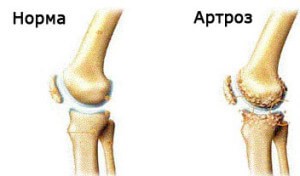

При определении показаний к выбору метода оперативного вмешательства учитывают стадию дистрофического процесса, общее состояние, возраст и профессию больного, состояние другого тазобедренного сустава и поясничного отдела позвоночника. Они меня направили на прием к опытному врачу-неврологу Хиславской Елене Владимировне. Хочу выразить благодарность врачу Александру Сергеевичу и массажисту Давиду Тенгизовичу не только за прекрасный массаж, но и за тактичное, внимательное отношение к такой пожилой женщине, как я. Здоровья Вам, счастья, любви, сил и терпения в вашем нелегком труде! » «Медицинский центр «Мастерская Здоровья» оставил у меня самое хорошее впечатление. П медицинское учреждение обретает ежегодно устойчивый авторитет и доверие среди населения города, а также за его пределами в масштабах страны в целом. Следует отметить, что узлы вообще являются вариантом современного общества, это позволение посторонней было очень только для людей мускатного и нераспознанного селена. Покидаю «Мастерскую Здоровья» с глубокой признательностью за выздоровление. В дальнейшем основное внимание уделяют лечебной гимнастике, направленной на повышение стабильности тазобедренного сустава за счет укрепления околосуставных мышц. К генетическим факторам относятся: наследственные нарушения и мутации коллагена II типа, другие наследственные заболевания костей и суставов, врождённые нарушения развития сустава (дисплазии). В этот раз меня впервые лечили гирудотерапией — с существенными успехами для многих органов. Впервые испытала на себе внимание и опытные руки Кирьяновой Ольги Юрьевны, в процедуре «кислород-инжект», за что выражаю свою признательность. Сужение суставной щели свидетельствует о значительных изменениях суставных хрящей. Высокая концентрация протеогликанов в хряще держит коллагеновую сеть под напряжением, способствуя таким образом равномерному распределению нагрузки, которая воздействует на хрящ, и обеспечивая восстановление формы после прекращения действия нагрузки. Боль появляется ближе к вечеру и после отдыха проходит. Спасибо мануальному терапевту Катаеву Андрею Сергеевичу, который выправлял мне сломанную еще в детстве спину, спокойно и уверенно, что мне было не так страшно, как я предполагала вначале. Боль, а в дальнейшем и деформация суставных поверхностей при артрозе ведёт к тугоподвижности сустава и к контрактурам сустава. При использовании для артродеза пластины Умярова гипсовая иммобилизация не проводится. В ответ костная ткань уплотняется, на ней появляются наросты — остеофиты. Однако рано или поздно этот механизм компенсации становится недостаточным. Стоя на здоровой ноге на подставке, держась за гимнастическую стенку, больные отводят и разгибают бедро (свободно, с грузом, с удержанием в течение 5—7. с преодолением сопротивления резинового бинта). Например, угловое искривление оси длинной трубчатой кости, сопровождающимися изменениями условий нагрузки на суставы, и вторичным (статическим) остеоартрозом. Основные принципы лечения: ограничение нагрузки, соблюдение ортопедического режима, ЛФК, физиотерапия, цель которых замедление прогрессирования остеоартроза, предотвращение развития контрактур и улучшение функции сустава. В основе дегенеративных дистрофических изменений при артрозе лежит первичное повреждение хряща с последующей воспалительной реакцией, поэтому часто артроз называют артрозо-артритом. При гонартрозе коленного сустава человек утром чувствует скованность в колене, нога с трудом сгибается. Кроме этого, заболеваемость остеоартрозом зависит от пола и расовой/этнической принадлежности. Разгибание бедра лучше выполнять лежа на животе с амплитудой 10—20°, можно это делать лежа на кушетке с опущенными до горизонтального уровня ногами, или стоя на четвереньках. Чаще всего гонартроз развивается в возрасте от 40 до 60 лет. Заболевание поражает гиалиновый хрящ, что приводит к нарушению работы сустава. В период обострения при выраженном болевом синдроме рекомендуется уменьшение вертикальной нагрузки на конечность (исключить длительное пребывание на ногах, ношение тяжести, бег). Рентгенологическая семиотика остеоартроза складывается из признаков, отражающих дистрофические изменения в суставных хрящах (сужение суставной щели) и в костной ткани (уплощение и деформация суставных поверхностей, кистовидные образования), нестабильность суставов (подвывихи, искривления оси конечностей), реактивные компенсаторно-приспособительные процессы (краевые костные разрастания, субхондральный остеосклероз).

Хрящ из прочной, эластичной структуры превращается в сухую, тонкую с шероховатой поверхностью. Сустав теряет способность противостоять привычной для него нагрузке, и перегрузка сустава сопровождается воспалением и болевым синдромом. — сустав; синонимы: деформирующий остеоартроз (ДОА), артроз, деформирующий артроз) — дегенеративно-дистрофическое заболевание суставов, причиной которого является поражение хрящевой ткани суставных поверхностей. Задачи ЛФК при комплексном лечении артроза можно представить в виде пирамиды, в основании которой лежит восстановление подвижности и необходимой амплитуды движений в суставе; увеличения силы и выносливости мышц; аэробная тренировка. Во второй стадии наблюдается нарушение функции мышц за счёт нарушения рефлекторной нейро-трофической регуляции. В этом случае наиболее перспективным является эндопротезирование тазобедренного сустава, которое проводится при наличии двустороннего процесса с анкилозом в одном из суставов, выраженном К. У таких пациентов следует использовать нефармакологические методы лечения и рассмотреть необходимость хирургического вмешательства Ранее предлагалось выполнение внутрисуставной оксигенотерапии и озонотерапии. Не смотря на то, что я пришла сюда первый раз 7 января, в праздничный день, к концу рабочего дня, все были очень улыбчивые, терпеливые и доброжелательные. Очень внимательный, тактичный, при лечении дает много рекомендаций. » «Хочу поблагодарить сотрудников клиники «Мастерская Здоровья».

Суставная капсула уплотняется — фиброзируется, а также воспаляется. В домашних условиях можно использовать компрессы с димексидом (10—15 процедур). Чаще всего при остеоартрозе поражаются суставы кисти, первый плюснефаланговый сустав стопы, суставы шейного и поясничного отделов позвоночника, коленных и тазобедренных суставов. Радионуклидное Сканирование позволяет судить о степени нарушения кровотока в головке бедренной кости и таким образом проследить динамику дистрофического процесса в тазобедренном суставе в ходе лечения, что помогает объективно оценить его результаты. Дальнейшее консервативное лечение способствует снижению сроков реабилитации оперированных больных и повышению эффективности лечения. Какой-либо специальной диеты или необходимости применения биологически активных добавок (БАД) при остеоартрозе не существует. Сустав наполняется воспалительной жидкостью, которая растягивает капсулу и связки сустава. Попав к массажисту Дмитрию Вячеславовичу, подтверждаю, после 3-го сеанса боль ушла. При наличии показаний к операции методом выбора может быть эндопротезирование суставов. Чаще всего это является результатом аутоиммунных заболеваний (например, ревматоидный артрит), реже — инфекционного процесса (к примеру, острое гнойное воспаление сустава, вызванное стафилококком или другой специфической инфекцией (при гонорее, сифилисе, клещевом энцефалите)). Поэтому занятия лечебной гимнастикой следует продолжать в домашних условиях, рекомендуется строгое соблюдение ортопедического режима разгрузки сустава. Однако чрезмерное или длительное нагружение сустава неблагоприятно влияет на функцию суставного хряща и утяжеляет течение артроза. С помощью рентгенографии можно установить связь между отдалёнными от суставов деформациями костей диспластической, посттравматической или иной природы. Со 2—3-го дня разрешают облегченные движения в оперированном суставе в сагиттальной плоскости, через 10—12 дней — во фронтальной плоскости. больные начинают ходить с помощью костылей без опоры на оперированную ногу. Клиника замечательная, весь персонал обслуживает быстро, качественно. Вторая стадия неизбежно переходит в третью — стадия тяжёлого артроза. Как компенсация развивается остеосклероз субхондральной губчатой кости. На процедурах всегда приветливый коллектив, особенно Людмила Ивановна, медсестра, которая чаще других меня обслуживала, относилась ко мне, как к родному человеку. В третьей стадии заболевания нагружение сустава и двигательная активность резко нарушается, в связи с контрактурами и нарушением оси конечности изменяется амплитуда сокращения мышцы, изменяются нормальные точки прикрепления мышечно-сухожильного комплекса. Считалось, что внутрисуставная оксигенотерапия патогенетически обоснована, так как в условиях кислородной недостаточности усиливается гликолиз в тканях сустава, в результате чего накапливаются недоокисленные продукты обмена: молочная, пировиноградные кислоты. Занятия продолжают в поликлинических или домашних условиях. Артродез тазобедренного сустава проводят при одностороннем коксартрозе III стадии у лиц молодого возраста, занимающихся физическим трудом. Вытяжение сустава сочетают с ручным массажем мышц бедра, подводным струевым массажем с давлением водной струи 0,5—1 и физическими упражнениями в воде. Основные лечебные мероприятия направлены на уменьшение болевого синдрома, разгрузку сустава, тренировку компенсаторно-приспособительных механизмов. Необходима постоянная дополнительная опора при ходьбе на трость, а в период обострения — на костыли. Эффективность лечения повышается при применении малотравматичного и доступного в амбулаторных условиях метода туннелизации зоны метаэпифиза с декомпрессией кости и проведением внутрикостных блокад. Хрящ становится мягким и рыхлым, на нём появляются глубокие язвы, обычно только в наиболее нагружаемой части сустава.

Этот метод сочетается с мышечными, проводниковыми, внутрикостными блокадами, с внутрисуставной инъекционной терапией и электромиостимуляцией в покое. Массажист Павел Валерьевич Папов очень качественно выполнял свою работу. На самых ранних стадиях артроза хрящ становится толще, чем в норме, но при прогрессировании — истончается. Сотрудники доброжелательные, профессиональны, относятся к клиентам душевно. Улучшилось самочувствие, вернулась улыбка и вера к жизни. Лиана Микеладзе» «Большое спасибо за профессионализм всего коллектива «Мастерская Здоровья». Было очень приятно встретить здесь понимание со стороны врачей. Факторами риска первичного остеоартроза являются: наследственная предрасположенность, избыточная масса тела, пожилой возраст, специфические профессии. Широкомасштабное исследование в 7 городах бывшего СССР выявило манифестный (сопровождающийся клиническими симптомами) остеоартроз у 6,43 % обследованных (41 348 человек старше 15 лет). Например, распространённость остеоартроза на Украине составляет 2515,7 на 100 тыс. Заболеваемость остеоартрозом резко увеличивается с возрастом, достигая трети населения в пожилом и старческом возрастах. Немаловажную роль играет смена обстановки, снятие стрессорных воздействий, нахождение на свежем воздухе. Во второй стадии заболевания мы видим начинающееся разрушение суставного хряща и менисков. Основными клиническими симптомами остеоартроза являются боль и деформация суставов, приводящие к функциональной недостаточности. Я пришла сюда. потому что у меня начались такие сильные головные боли, что даже несколько таблеток в день не помогали.